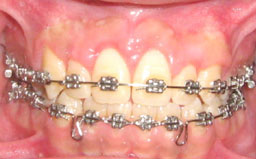

2ème cas clinique :

![]() |

Fig 10 et 11 : la hauteur de gencive kératinisée/attachée serait insuffisante après gingivectomie puisqu’elle est formée surtout de gencive libre: un lambeau déplacé apicalement a été réalisé afin de conserver au maximum la hauteur de gencive kératinisée.

Des sutures périostées ont permis d’apicaliser le lambeau.